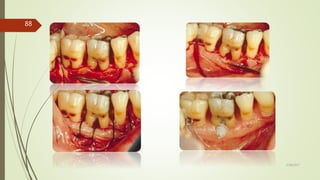

 During surgery, bone is

reshaped to obtain a scalloped

morphology and the soft tissues

are apically positioned

 Care must be taken that the

space obtained under the roof

of the furcation should allow

proper plaque removal